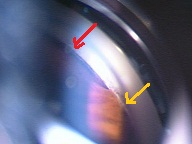

黄斑円孔の手術に関しては、?で記載しましたが、簡単におさらいすると、目の中に器械をいれて、内境界膜という網膜の表層の膜を剥離し、網膜を柔らかくします。その後、目の中に空気を入れてうつ伏せをすることで、円孔の周囲の網膜を浮力で引き寄せて、穴を閉じる。という方法です。

?黄斑円孔で、赤の部分の網膜が硝子体に引っ張られて断裂し、無くなってしまうと、視野の中心部が欠損、見たい部分が見えなくなってしまいます。